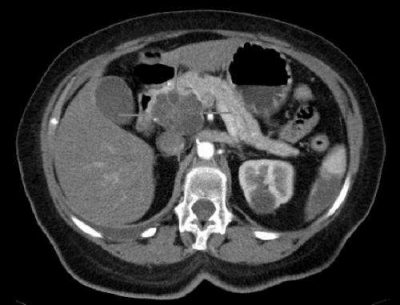

Cancro al pancreas-immagine: immagine TC assiale con contrasto endovenoso. Adenocarcinoma macrocistico della testa del pancreas. Credito: pubblico dominio.